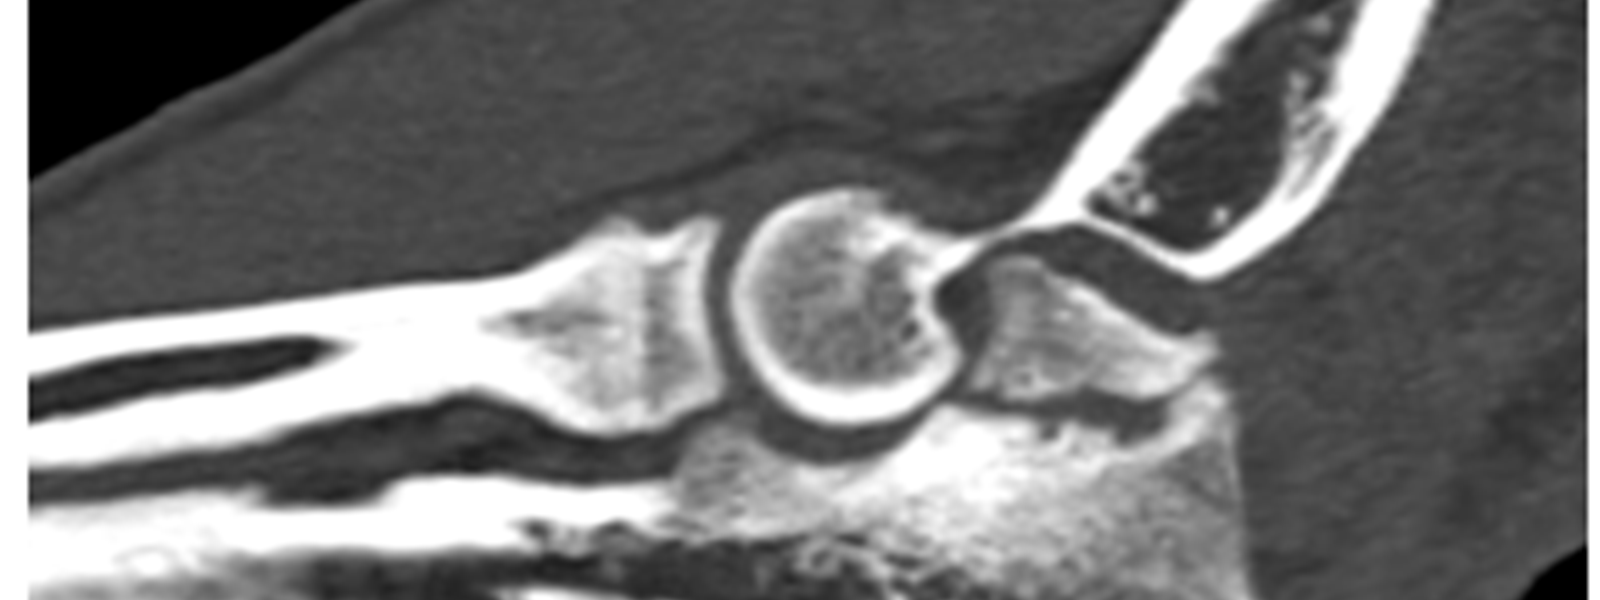

The elbow is a complex, tight fitting “hinged” joint made up by the end of the humerus and both the radius and ulna. It is controlled by a number of different muscle groups and its function is fundamental to gait.